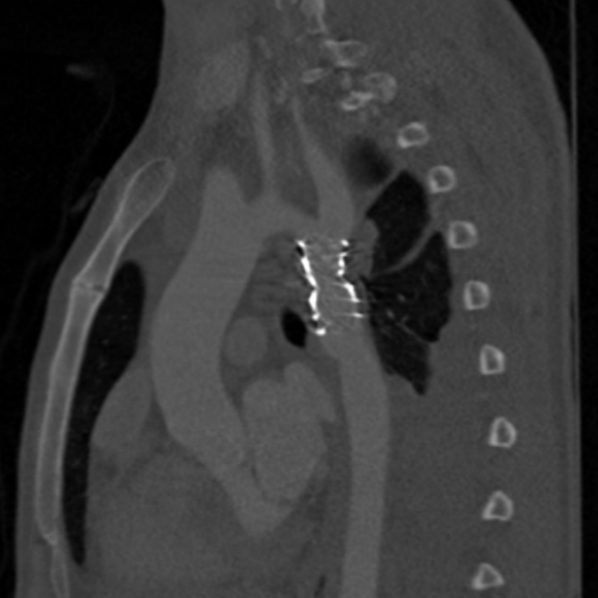

患者术后6个月复查CTA显示支架位置理想,且无并发症。

术后CTA影像